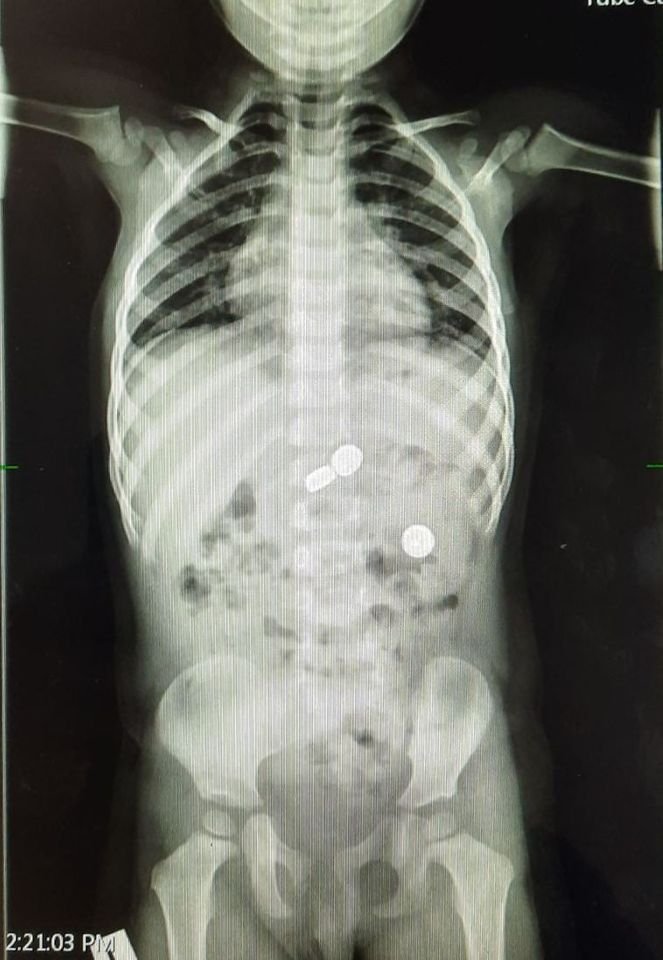

18 ноября в клинику обратились родители 2-летнего ребенка, из-за того, что в рвотных массах малыша обнаружили батарейку. После рентгенограммы стало понятно, что ребенок съел не одну, а целых 4 батарейки. Так, еще две из них находились в желудке, одна - в кишечнике. Две батарейки были удалены из желудка под седацией (введение пациента в состояние полудремы при помощи “